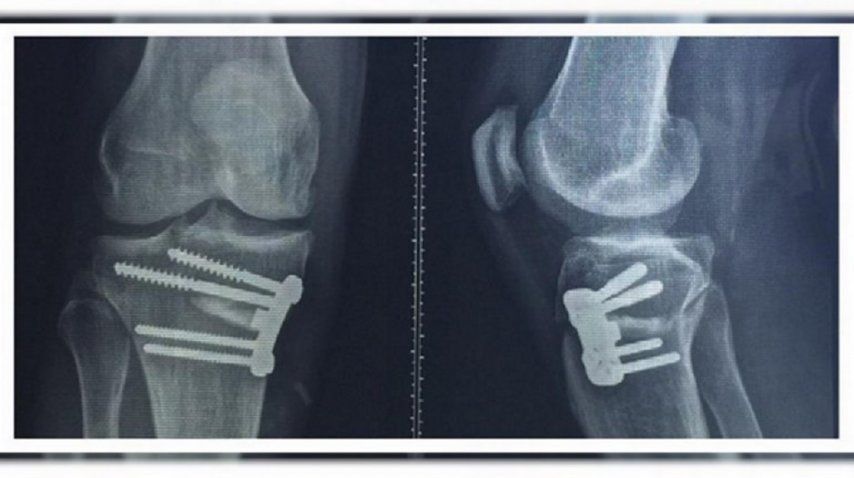

Sólo 30 días después de su retiro profesional, debió operarse por primera vez en su carrera su rodilla derecha. Mientras se recupera, publicó una foto a su cuenta de Instagram, mostrando las condiciones en que se encuentra su pierna.Allí se pueden ver en detalle los tornillos que debieron colocarle en el centro médico de Corinthians para adecuar la zona afectada. "Había jugado cuatro partidos y me había hecho todo tipo de infiltraciones. Pero tengo 43 años y la salud es lo primero", informó el brasileño que también brilló con las casacas del Milan, Palmeiras y La Coruña.